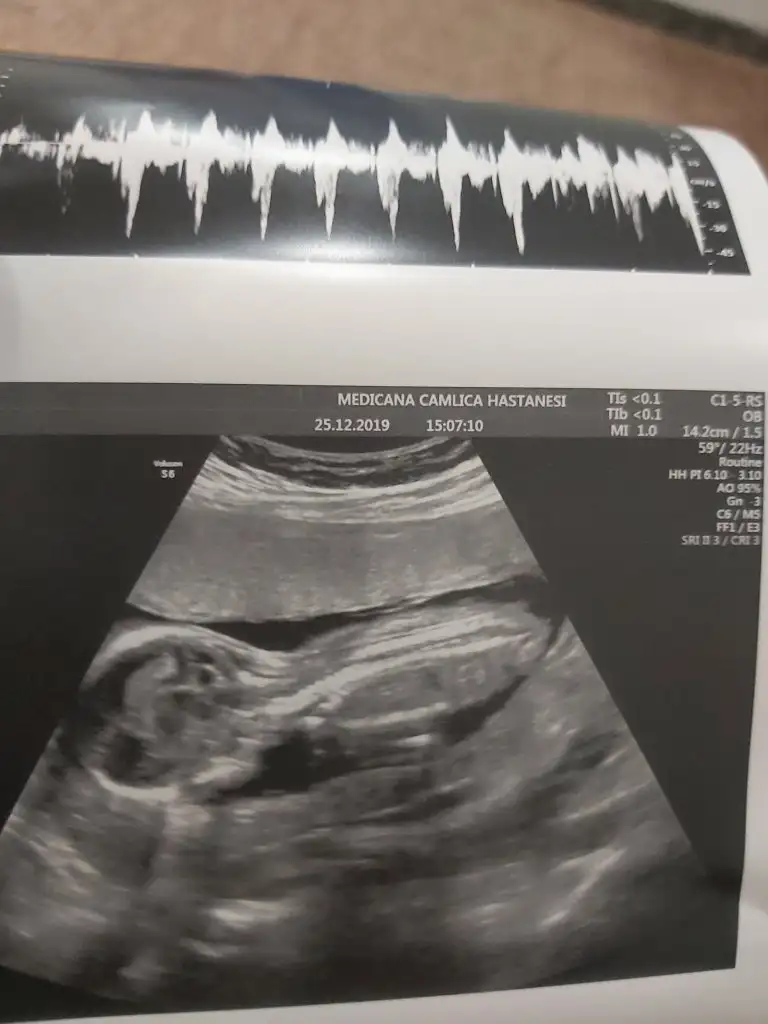

dr soylemeden siz gorun genital nub teorisi ( bebegin cinsiyeti)

Siz de yine bakarmısınız net söyledi kız diye herkes erkek demişti sizin gibi bende öyle diyordum ama ters köşe yaptı galiba bizimki çok hareketliydi 🤭🤣

• 20191225_151538.webp

20191225_151538.webp

20,7 KB · Görüntüleme: 37